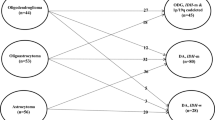

Twenty-six patients with a mean age of 66 years met inclusion criteria with a median follow-up of 5.2 years. Diagnoses included diffuse astrocytoma IDH-mutant (19.2%), diffuse astrocytoma IDH-wildtype (26.9%), Oligodendroglioma IDH-mutant and 1p/19q-codeleted (50%), and a rare case of mixed oligoastrocytoma (3.9%). 66% of astrocytoma IDH-wildtype tumors possessed TERT mutation. Median extent of resection was 75.4%. Progression-free (PFS) and overall survival (OS) were 23.5 and 62.6 months, respectively. Shorter PFS was associated with the astrocytoma IDH-wildtype subtype despite similar extent of resection and adjuvant treatment rates compared to the other subtypes. OS did not differ between subtypes. Malignant transformation and death were associated with larger preoperative and residual tumor volume.

Demographics and tumor characteristics are listed in Table 1. The mean age at the time of surgery was 66.2 years (range 60.3–76.7) with a median follow-up of 5.2 years (range 0.4–12.4 years). The majority of tumor involved the frontal lobe (38.5%) and were left-sided (57.7%). Pathologic diagnoses based on the updated 4th edition of WHO classification included five cases of diffuse astrocytoma, IDH-mutant, seven cases of diffuse astrocytoma, IDH-wildtype, and 15 cases of oligodendroglioma, IDH-mutant and 1p/19q-codeleted. There was one case designated as a mixed oligoastrocytoma. For this case, histology demonstrated distinct regions of oligodendroglioma and astrocytoma morphology. The oligodendroglioma-like component showed IDH1 R132H mutation, 1p/19q-codeletion, retained ATRX expression and negative p53 staining, and astrocytoma-like component demonstrated IDH1 R132H mutation, loss of ATRX expression, intact 1p/19q and wildtype TERT promoter. Further molecular characterization of the diffuse astrocytoma, IDH-wildtype tumors demonstrated that 66.7% harbored a TERT promoter mutation (Table 2). There were five cases (19.2%) with enhancement on preoperative imaging, which was not significantly associated with any particular subtype (see Table 2). Mean preoperative tumor volume was found to be 58.8 cm3.

Long-term clinical outcomes

Long-term outcomes are summarized in Table 3. Median censored PFS and OS were found to be 23.5 and 62.6 months, respectively. Nine cases (34.6%) on follow-up demonstrated malignant transformation. Table 2 depicts treatment characteristics and differences in clinical outcomes between the glioma molecular subtypes. Although EOR and adjuvant therapy did not significantly differ between the three molecular subtypes, diffuse astrocytoma IDH-wildtype cases were associated with a significantly shorter PFS (Fig. 1a; Table 2). However, molecular subtype did not appear to significantly impact overall survival (Fig. 1b; Table 2). Univariate analysis of other patient, tumor, and treatment features associated with PFS and OS did not reveal any significant associations (Table 4). Larger preoperative tumor size and a greater amount of residual tumor on postoperative scans were associated with more frequent malignant progression and death (Table 5). Contrast enhancement was not associated with a difference in PFS, OS, or malignant transformation.